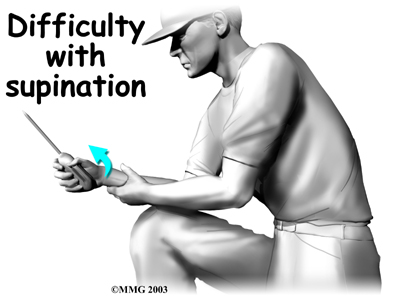

can bend the elbow upward. The biceps can also help flex the shoulder, raising the arm up. And the biceps can rotate, or twist, the forearm in a way that points the palm of the hand up. This movement is called . Supination positions the hand as if you were carrying a tray.

Not having surgery often results in significant loss of strength. Flexion of the elbow is somewhat affected, but supination (which is the motion of twisting the forearm, such as when you use a screwdriver) can be very affected. A distal biceps rupture that is not repaired reduces supination strength by about 50 percent.